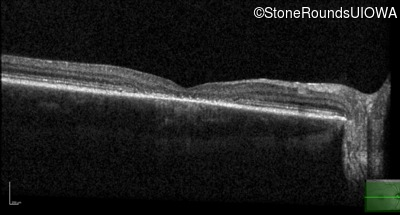

Optical Coherence Tomography - Right - 20/80 -1

Exemplar / OCT Stack